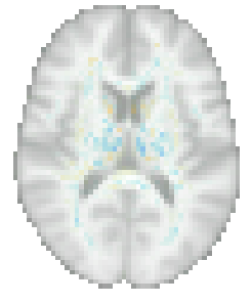

More insight can be gained by examining the proposed method specifically, since it uses disciminative maps that are derived from generative ones. It is worth noting that estimating the generative maps from training data is itself quite stable, since it merely amounts to fitting two basis functions to hundreds of measurements in each voxel (cf. (8)). Furthermore, as illustrated in Fig. 10, the resulting maps are intuitive to interpret, since they show typical age-related effects such as cortical thinning and ventricle enlargement (Fjell et al., 2009; Fjell and Walhovd, 2010). When the discriminative maps are subsequently computed as , however, a strong dependency on the training set size is introduced, because the method explicitly controls the complexity of its noise model in response to the size of the available training set (the bias-variance trade-off of Sec. 4.4). can also capture peculiarities in the data that may be relevant for improving prediction performance, but not for human interpretation. An example of this was shown in Fig. 5, where overall brightness variations and residual MR bias field artifacts were picked up by the noise model. Through , such noise patterns can find their way into , producing hard-to-interpret spatial maps that no longer reflect the expected age-related brain atrophy patterns. This is clearly illustrated in Fig. 4, where the discriminative map is contrasted with the corresponding generative map .

In addition to visualizing its generative maps directly for human interpretation, the causal interpretation of our model can also be used to simulate the effect of aging on actual images. On the population level, this can be achieved by computing age-specific templates for different values of , as illustrated in Fig. 12. More detailed explanations can also be provided at the level of the individual subject, using counterfactuals (Pearl and Mackenzie, 2018) – imaginary images of specific individuals if they had been younger or older. Given an image and the real age , (10) can be used to compute the subject-specific noise vector , which captures the subject’s individual idiosyncrasies that are not explained by the population-level causal model. Counterfactual images can then be obtained by re-assembling the forward model from its constituent components, using a different, imaginary age in (1). Examples of this process are shown in Fig. 13.